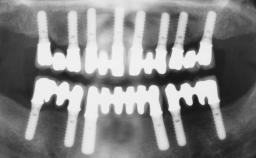

Immediate Loading of Six Implants in the Maxilla and Final Restoration with a Full-Arch CAD/CAM Zirconia FDP

# of Implants 6

Type of Implants One-Piece